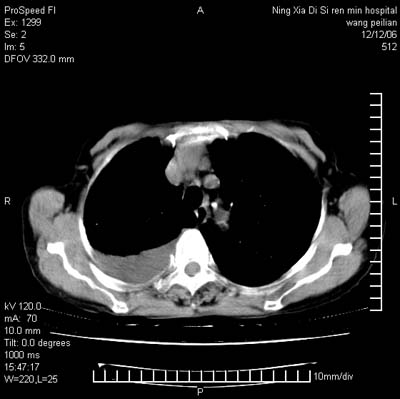

标题: CT5609:胸部:女77 病史不详

两肺可见多个大小不等的结节,左侧有胸水,纵隔淋巴结增大,考虑是细支气管肺泡癌

两肺尖纤维索状影,两下肺结节块状影,且有钙化灶,右胸腔积液。考虑肺结核并胸膜炎。

两肺尖纤维索状影,两下肺结节块状影,且有钙化灶,右胸腔积液。考虑肺结核并胸膜炎肺间质纤维化

考虑:1、慢性支气管炎合并全小叶型肺气肿、间质纤维化;

2、双肺结核;

3、右侧胸膜炎(积液)。

1、双肺继发型肺结核(以纤维、增殖灶为主);

2、右侧胸腔积液;

3、其余符合老年肺改变。

双肺见多个结节状及条索状影,双侧胸腔积液,右侧叶间积液,考虑结核性胸膜炎